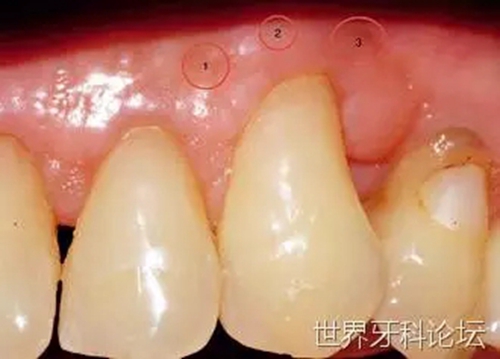

一位52歲女性患者,患局限型重度牙周炎。急性炎癥穩(wěn)定后,對(duì)患者進(jìn)行檢查,#23遠(yuǎn)中發(fā)現(xiàn)明顯的深骨內(nèi)袋(圖1)。瓣的設(shè)計(jì)同時(shí)考慮到解決目前的牙齦退縮(圖2)。仔細(xì)清創(chuàng),去除肉芽組織(圖3),之后,植入無機(jī)小牛來源羥基磷灰石(圖4)。

圖2:牙齦退縮。

一位41歲男性患者,下前牙嚴(yán)重的創(chuàng)傷性牙齦退縮。經(jīng)過仔細(xì)咨詢后,患者預(yù)約進(jìn)行膜齦手術(shù)(圖8)。因缺少角化牙齦且前庭溝淺,唯一的治療方法是進(jìn)行游離牙齦移植以覆蓋根面。

圖8:膜齦手術(shù)前。